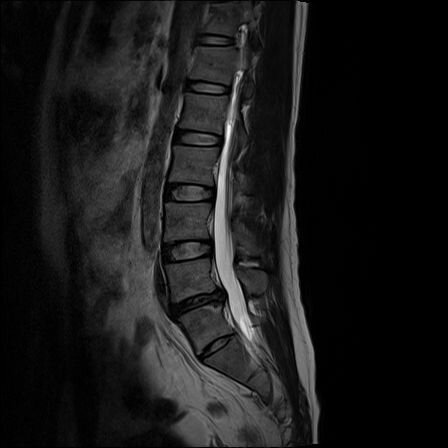

1. Снимки МРТ и (если есть) рентген поясничного отдела позвоночника, сделанные за последние 3 месяца